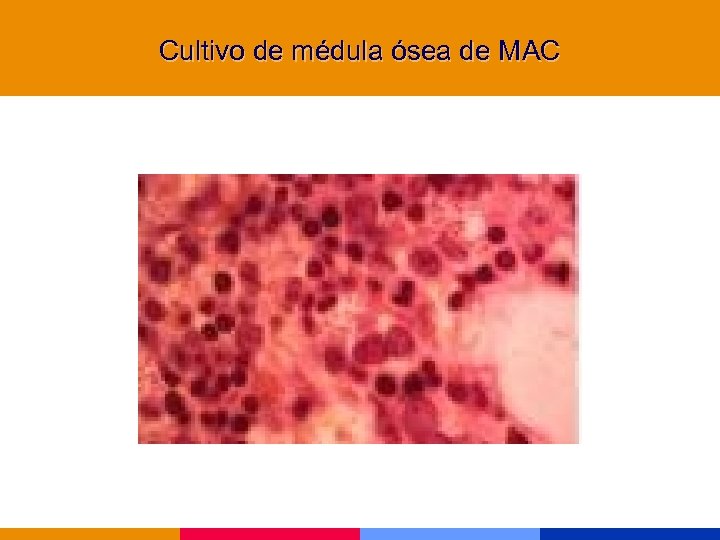

Cultivo de médula ósea de MAC

Cultivo de médula ósea de MAC